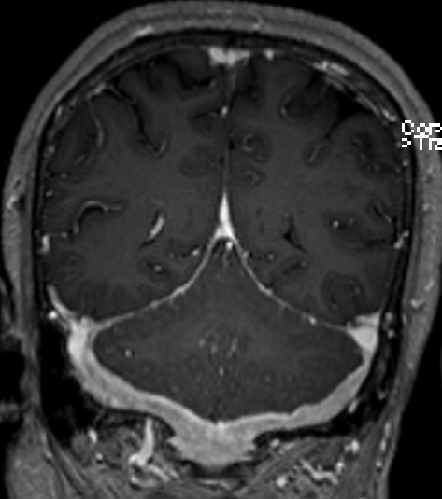

2015-4-1 MRI

2013-5-16

2013-8-2

2014-12-13

2015-4-1

2015-4-3